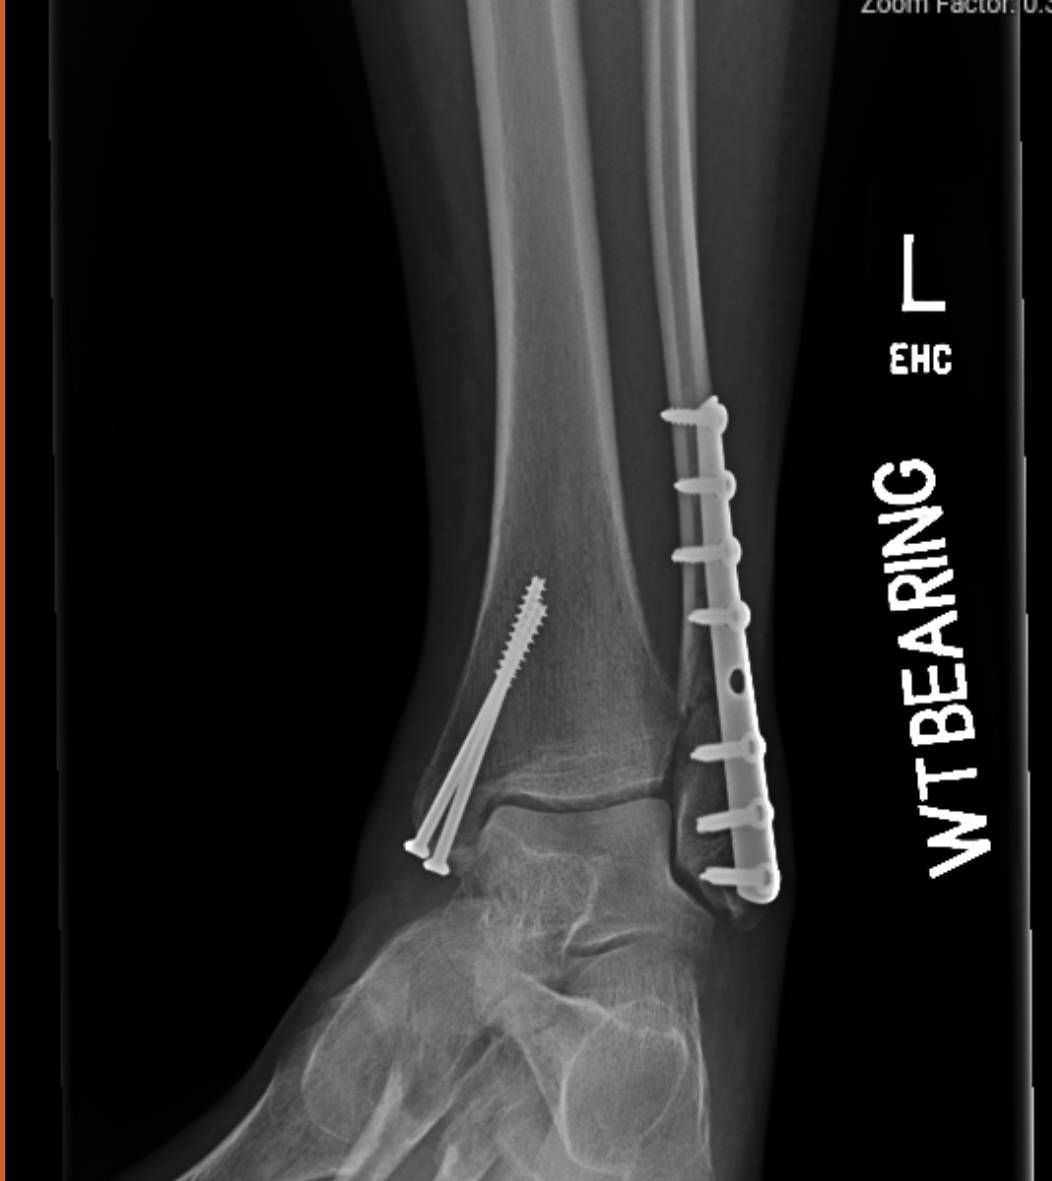

ORIF of Left Ankle Fracture 1017 PI Exhibits NOW! Running After Ankle Orif A little pain can be expected but you shouldn't be in agony a day later. If your ankle feels okay try and do a short run, taking it easy. This protocol provides a general guideline for recovery and progression of rehabilitation according to specified time. Ankle fractures are common and frequently managed using open reduction and internal fixation (orif). •. Running After Ankle Orif.